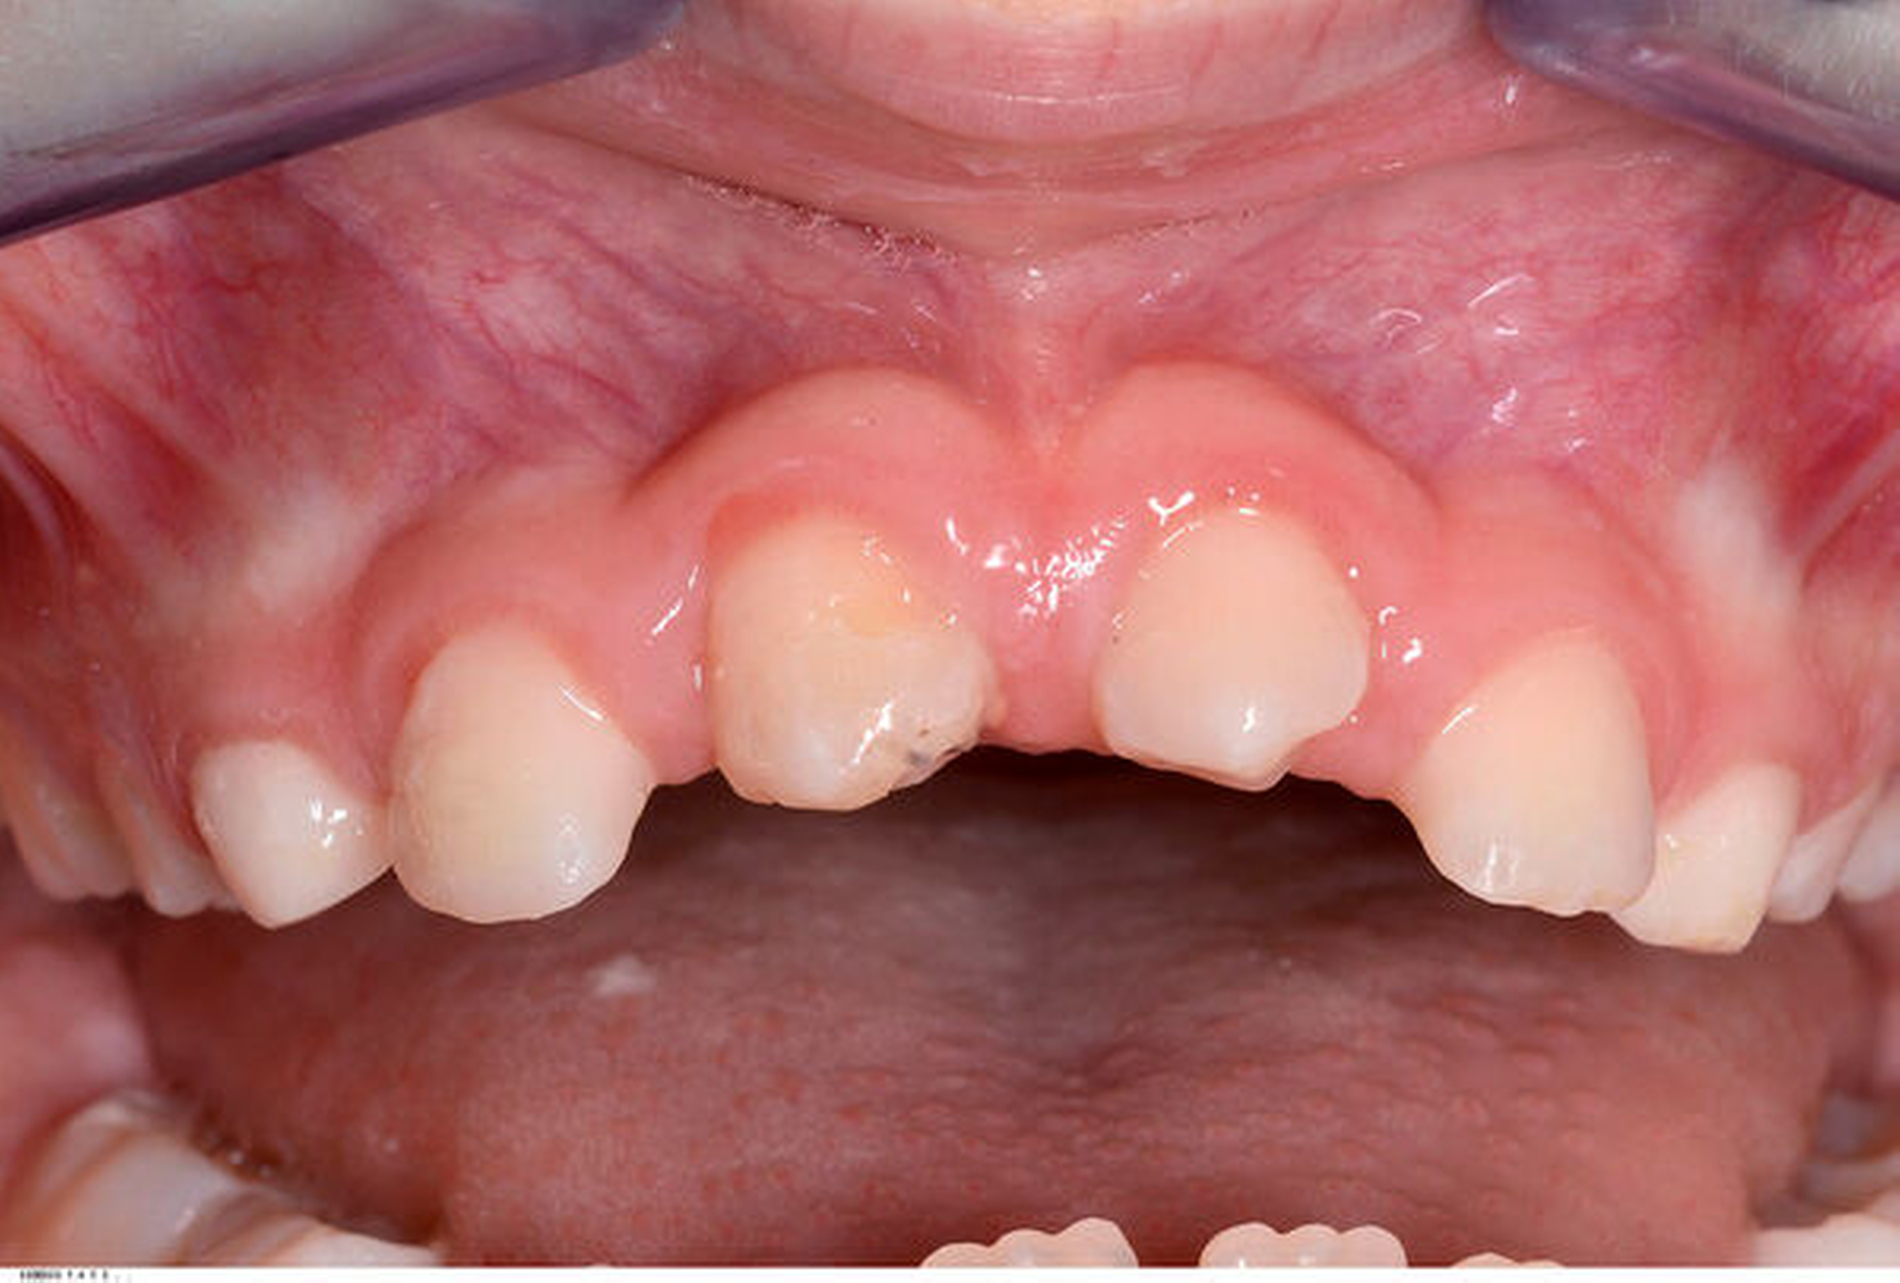

Die Rekonstruktion von Zähnen mit Komposit ermöglicht eine direkte und maximal zahnerhaltende Therapie, bei der die Zahnhartsubstanz nicht oder nur minimal im Sinne einer Anschrägung abgetragen werden muss. Im Vergleich zur Rekonstruktion mit keramischen Veneers muss dabei in der Regel wesentlich mehr Zahnhartsubstanz geopfert werden, um die nötigen Keramikschichtstärken einhalten zu können. Reparaturen, Farb- und Formanpassungen lassen sich mit der Komposittechnik im Vergleich zu Keramikrestaurationen immer wieder anpassen. Insbesondere bei jungen Patienten im Wachstum ist dies von Vorteil, um bei Veränderungen der Gingivaverhältnisse die rekonstruierten Zähne ihren Nachbarzähnen anzupassen (Verschluss schwarzer Dreiecke, zervikale Ausformungen).

In beiden Falldarstellungen wurden diese Bedingungen eingehalten. Eine Besonderheit stellt die Kombination von kieferorthopädischem Lückenschluss und Autotransplantation im zweiten Fall dar. Hier war vor der Rekonstruktion mittels Kompositaufbau eine Bewegung des Transplantats und der rechten Seitenzahnreihe erforderlich. Beides gestaltete sich ohne Probleme und sollte auch beim Verlust mehrerer Schneidezähne bedacht werden. Der Lückenschluss im Unterkiefer nach Keimentnahme konnte mithilfe skelettaler Verankerung ebenfalls reibungslos erfolgen. Es sollte jedoch wie beim kieferorthopädischen Lückenschluss die Anlage der dritten Molaren in der verkürzten Zahnreihe geprüft werden, um für den zweiten Molaren des Gegenkiefers einen Antagonisten zu haben. Ziel des Beitrags war es, die Autotransplantation nach Frontzahnverlust und Aplasie ins differenzialdiagnostische und -therapeutische Spektrum als gleichberechtigte Variante einzubeziehen.